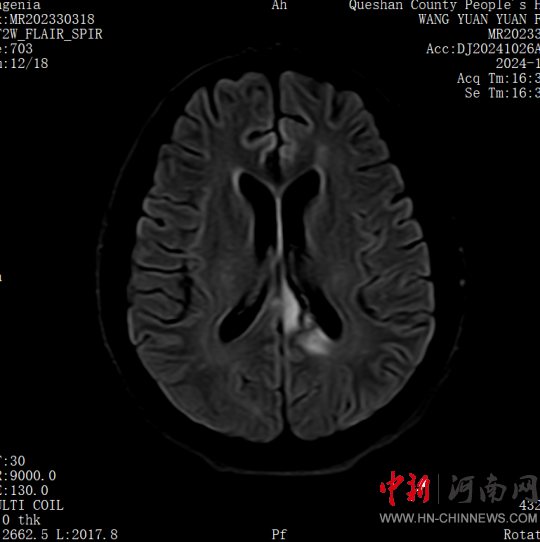

患者,女,32歲,車禍傷,到達確山縣人民醫(yī)院急診科創(chuàng)傷中心救治時血壓80/45mmHg,心率115次/分,處于昏迷、休克狀態(tài),病情危重。急診科迅速啟動創(chuàng)傷中心急救綠色通道,醫(yī)護人員立即展開搶救,積極抗休克治療的同時,聯(lián)系神經(jīng)外科、胸外科、急診重癥監(jiān)護室緊急會診,同時快速CT、床旁FAST檢查明確診斷。通過一系列急救措施,患者的休克狀態(tài)稍微好轉(zhuǎn),經(jīng)多學(xué)科會診后明確診斷為:多處損傷并失血性休克、彌漫性軸索損傷、蛛網(wǎng)膜下腔出血、腦挫傷、股骨及脛腓骨粉碎性骨折、多發(fā)肋骨骨折并肺挫傷、腰椎骨折。ISS評分高達50分,死亡率極高,患者病情危重,立即送入急診重癥監(jiān)護室進行高級生命支持治療。